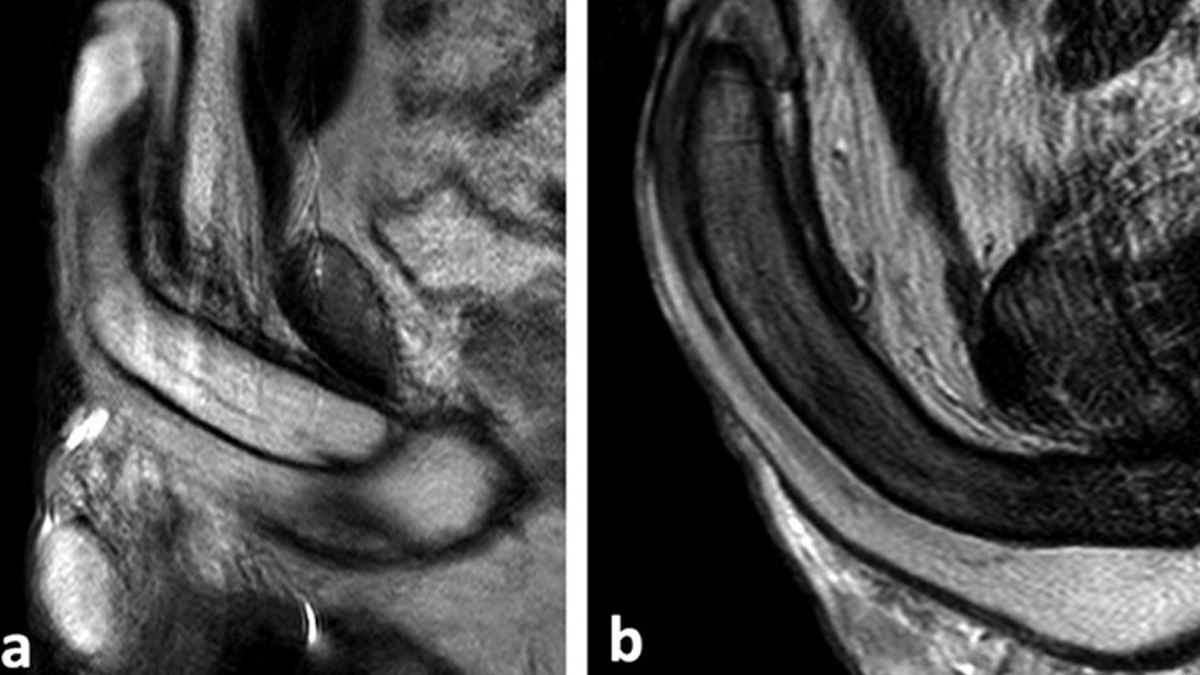

Blood gets trapped in the penis and cannot leave. “In the ischemic variety, blood gets trapped in the corpora cavernosa (two sponge-like cylinders of erectile tissue in the penis that fill with blood to enable an erection) with no exit path. This condition is far more dangerous than the non-ischemic type. The penis becomes rigid and painful, and as time ticks by, the oxygen in the trapped blood depletes, leading to tissue death. It would not be an exaggeration to say that delay in hospital care may result in a man losing his ability to ever have a natural erection again.” In India, many cases are linked to sickle cell disease and thalassemia. Other causes include erectile dysfunction medicines, recreational drugs, and psychiatric medications. Young men often delay seeking help due to embarrassment.

Usually caused by injury to the pelvis or perineum. “In contrast, non-ischemic priapism, usually caused by trauma, often a pelvic or perineal injury, presents differently. It is not as painful, and the urgency is lower since the erection is semi-rigid. These patients typically don’t face an emergency, but they need evaluation nonetheless.”